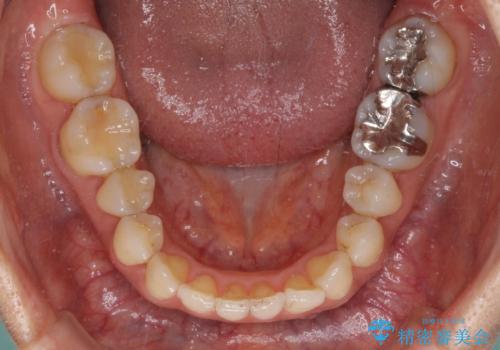

- 矯正治療の後戻りを気にして来院された患者様です。

後戻りは軽微であったので、インビザライン・ライトにより矯正治療を行うこととしました。